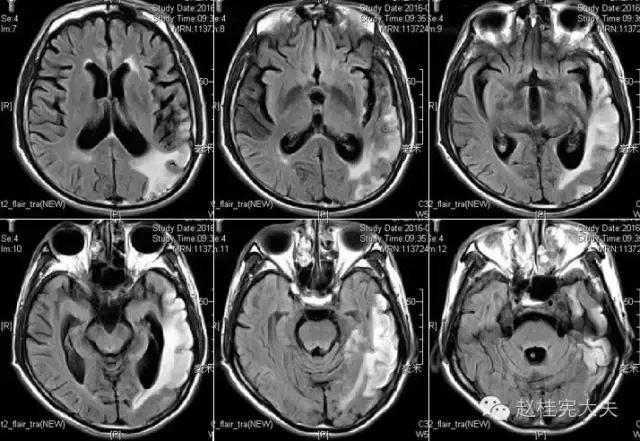

上周,于发病后2月复查磁共振:

到此为止,MELAS的诊断应该在没有基因确诊的情况下在临床上得到认可了,患者明确诊断为线粒体脑肌病伴乳酸血症和卒中样发作(MELAS),解释了患者的所有症状,患者母亲不明原因地死亡也得以真相大白,患者的相关亲属们在未来的人生路上也多了一份呵护......